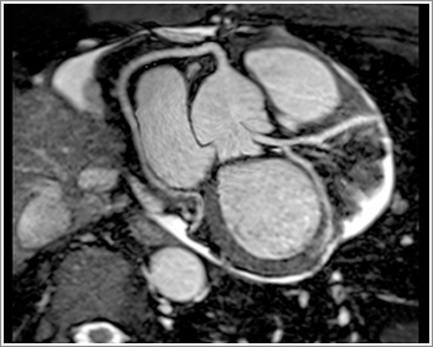

الرنين المغناطيسي على أنجيو الشرايين (MR Angiography)

يُعد الرنين المغناطيسي على أنجيو الشرايين من أحدث تقنيات تصوير الشرايين والأوعية الدموية، حيث يتيح تقييمًا دقيقًا للشرايين التاجية والأوعية الكبرى دون الحاجة إلى تدخل جراحي أو قسطرة.

يساعد هذا الفحص المتقدم في:

- تشخيص ضيق وانسداد الشرايين التاجية

- تقييم أمراض الأوعية الدموية المختلفة

- متابعة حالات تصلب الشرايين

- دعم التشخيص الدقيق ووضع الخطة العلاجية المناسبة

ويتميّز الرنين المغناطيسي على أنجيو الشرايين بأنه:

- عالي الدقة في إظهار تفاصيل الأوعية الدموية

- آمن في كثير من الحالات مقارنة بالفحوصات التداخلية

- مناسب للمتابعة طويلة المدى لبعض مرضى القلب والشرايين